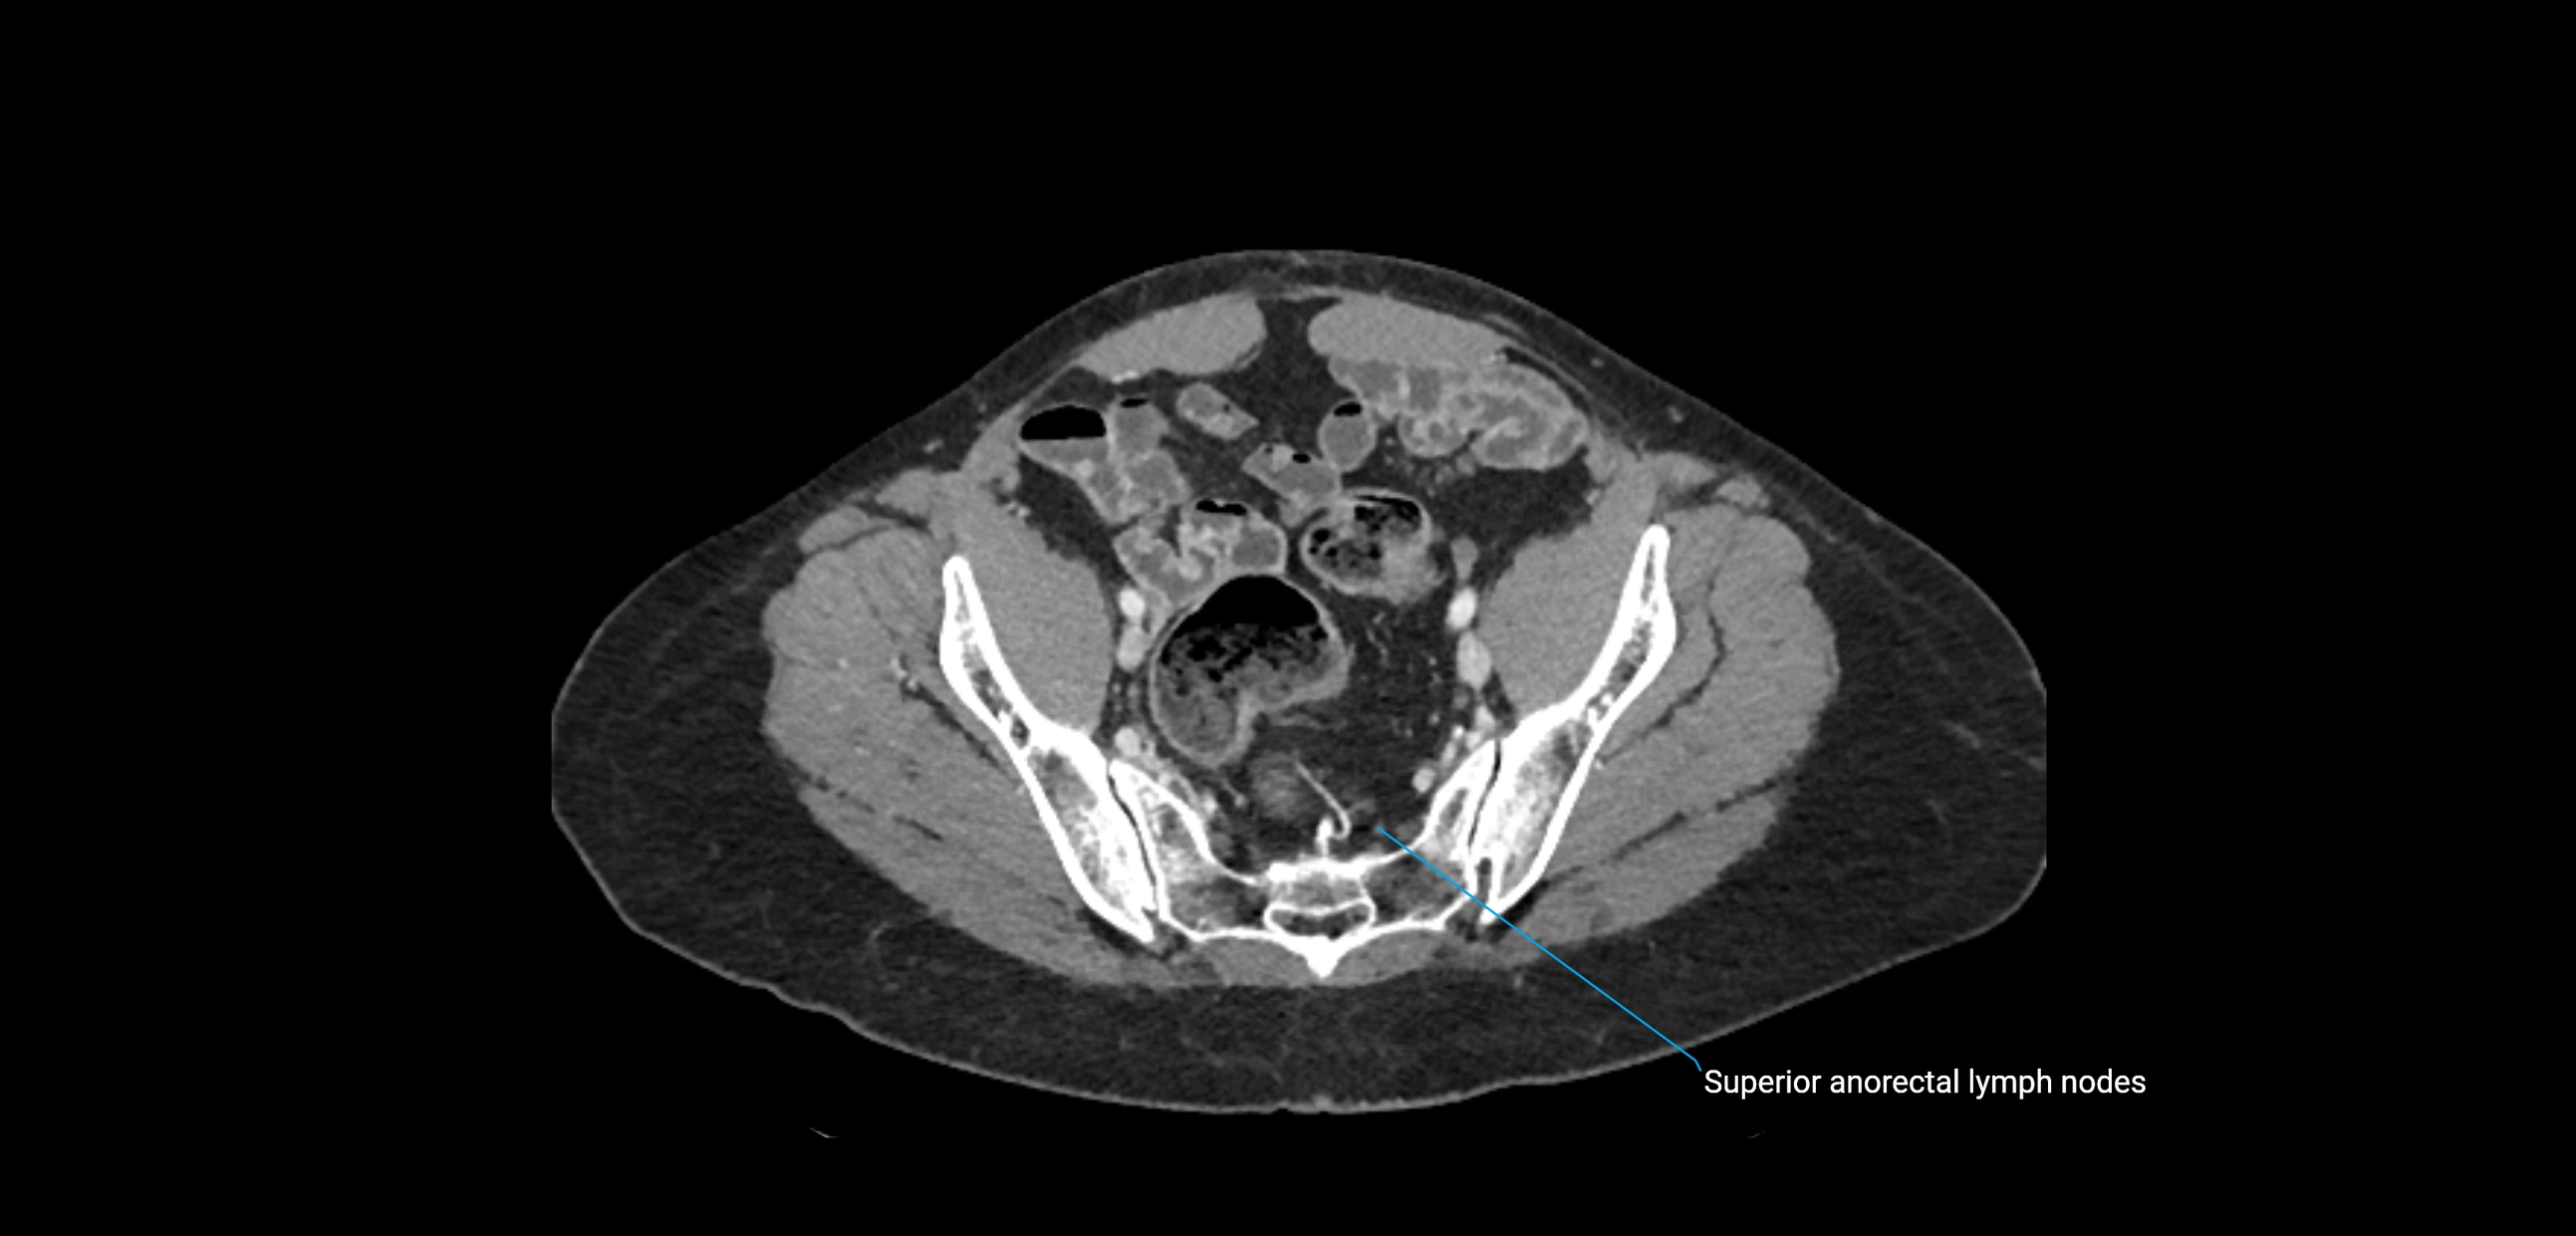

CT Appearance

CT Post-Contrast:

• Normal nodes enhance homogeneously

• Malignant nodes may show heterogeneous enhancement, central necrosis, or conglomerate formation

• Size >1 cm short axis is suspicious, though morphology and distribution are equally important

CT Venography (CTV):

• Demonstrates nodal encasement or compression of adjacent vessels (aorta, IVC, renal veins)

• Useful in staging testicular and ovarian malignancies

• Provides 3D reconstructions for retroperitoneal lymph node dissection planning